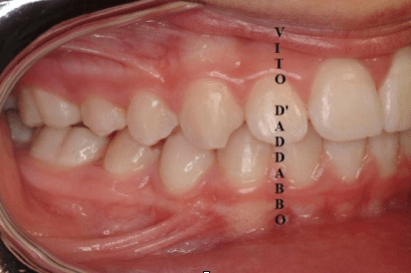

In una bocca che chiude correttamente i denti dell’arcata superiore sono collocati più esternamente rispetto ai corrispondenti dell’arcata inferiore. Nel morso inverso accade il contrario: in quello laterale sono i denti inferiori laterali a chiudere esternamente.

Questa malocclusione è il più delle volte dovuta a un mascellare piccolo, come nel caso riportato, dove manca anche lo spazio per l’incisivo laterale permanente di sinistra. I morsi incrociati vanno corretti precocemente perché possono provocare gravi asimmetrie del viso.

dopo